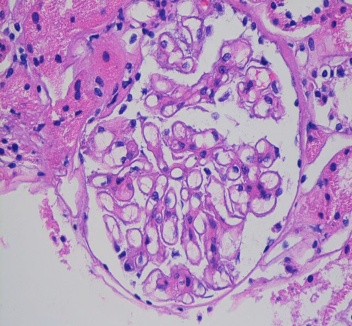

为了找到真凶,医生为老刘做了肾脏穿刺活检病理检查。病理结果是:膜性肾病。

真相终于大白: 是这个早期的肾脏肿瘤,刺激免疫系统产生了异常反应,免疫复合物像垃圾一样堵塞了他的肾小球,导致蛋白质大量漏出,最终表现为水肿和蛋白尿。外科医生为老刘试行了手术及后续治疗。手术后,老刘的蛋白尿和水肿也逐渐消失了。